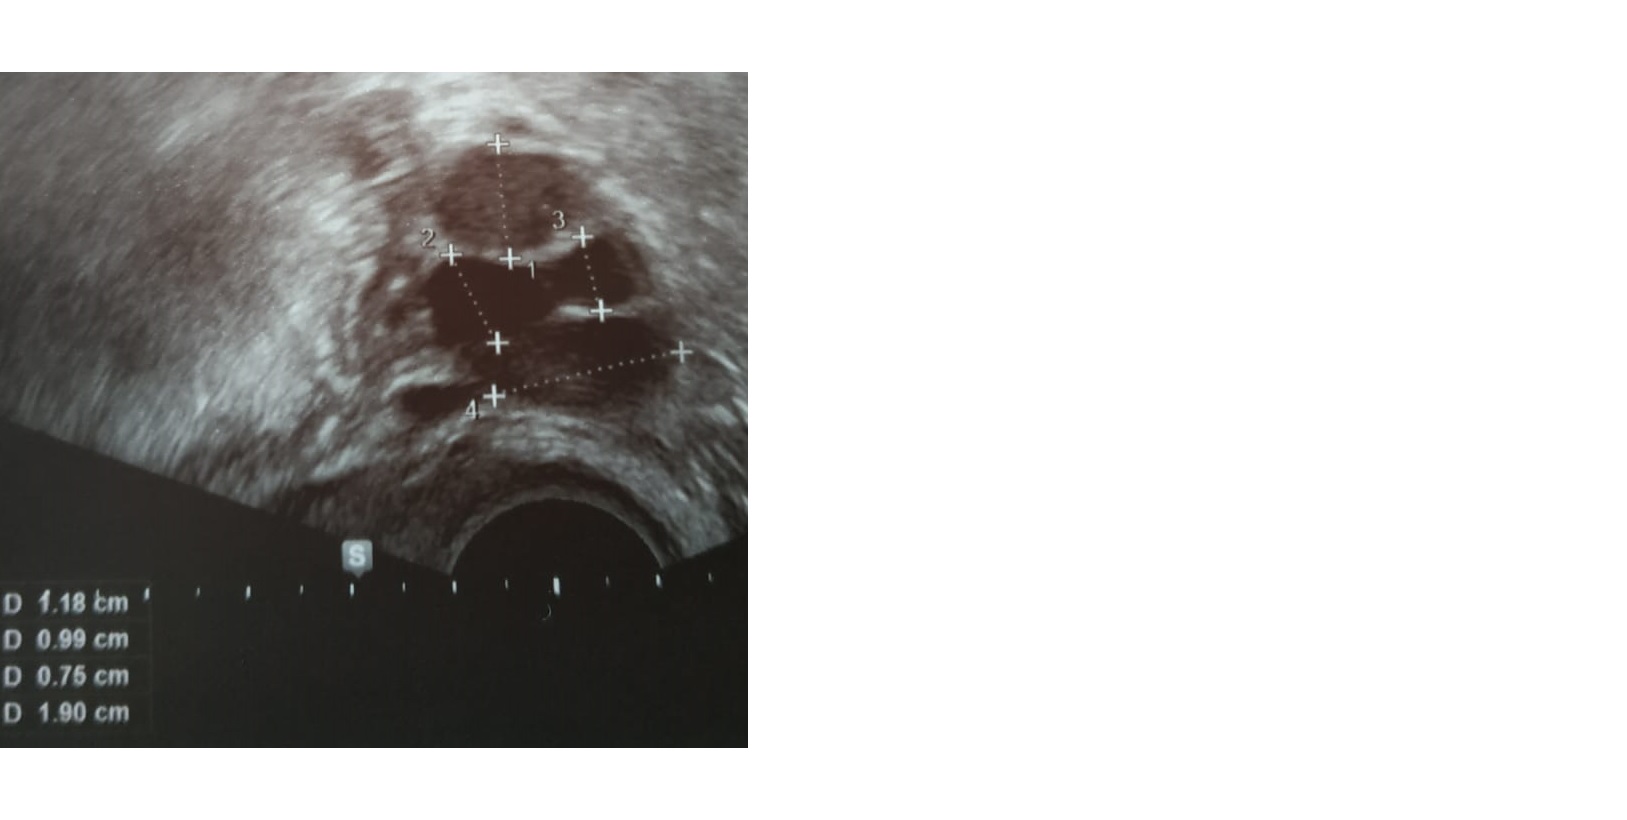

Heute Zyklustag 7 war ich zur Kontrolle, meine SH ist bei 9,3 mm und links sieht man 3 Stück.

Eins bei 20,8 mm und zwei bei 13,7 mm - mein Frauenarzt konnte aber nicht sagen ob das bei 20,8 mm der Follikel wäre oder die Zyste...

Als Anlage auch das Bild von meinem Frauenarzt.